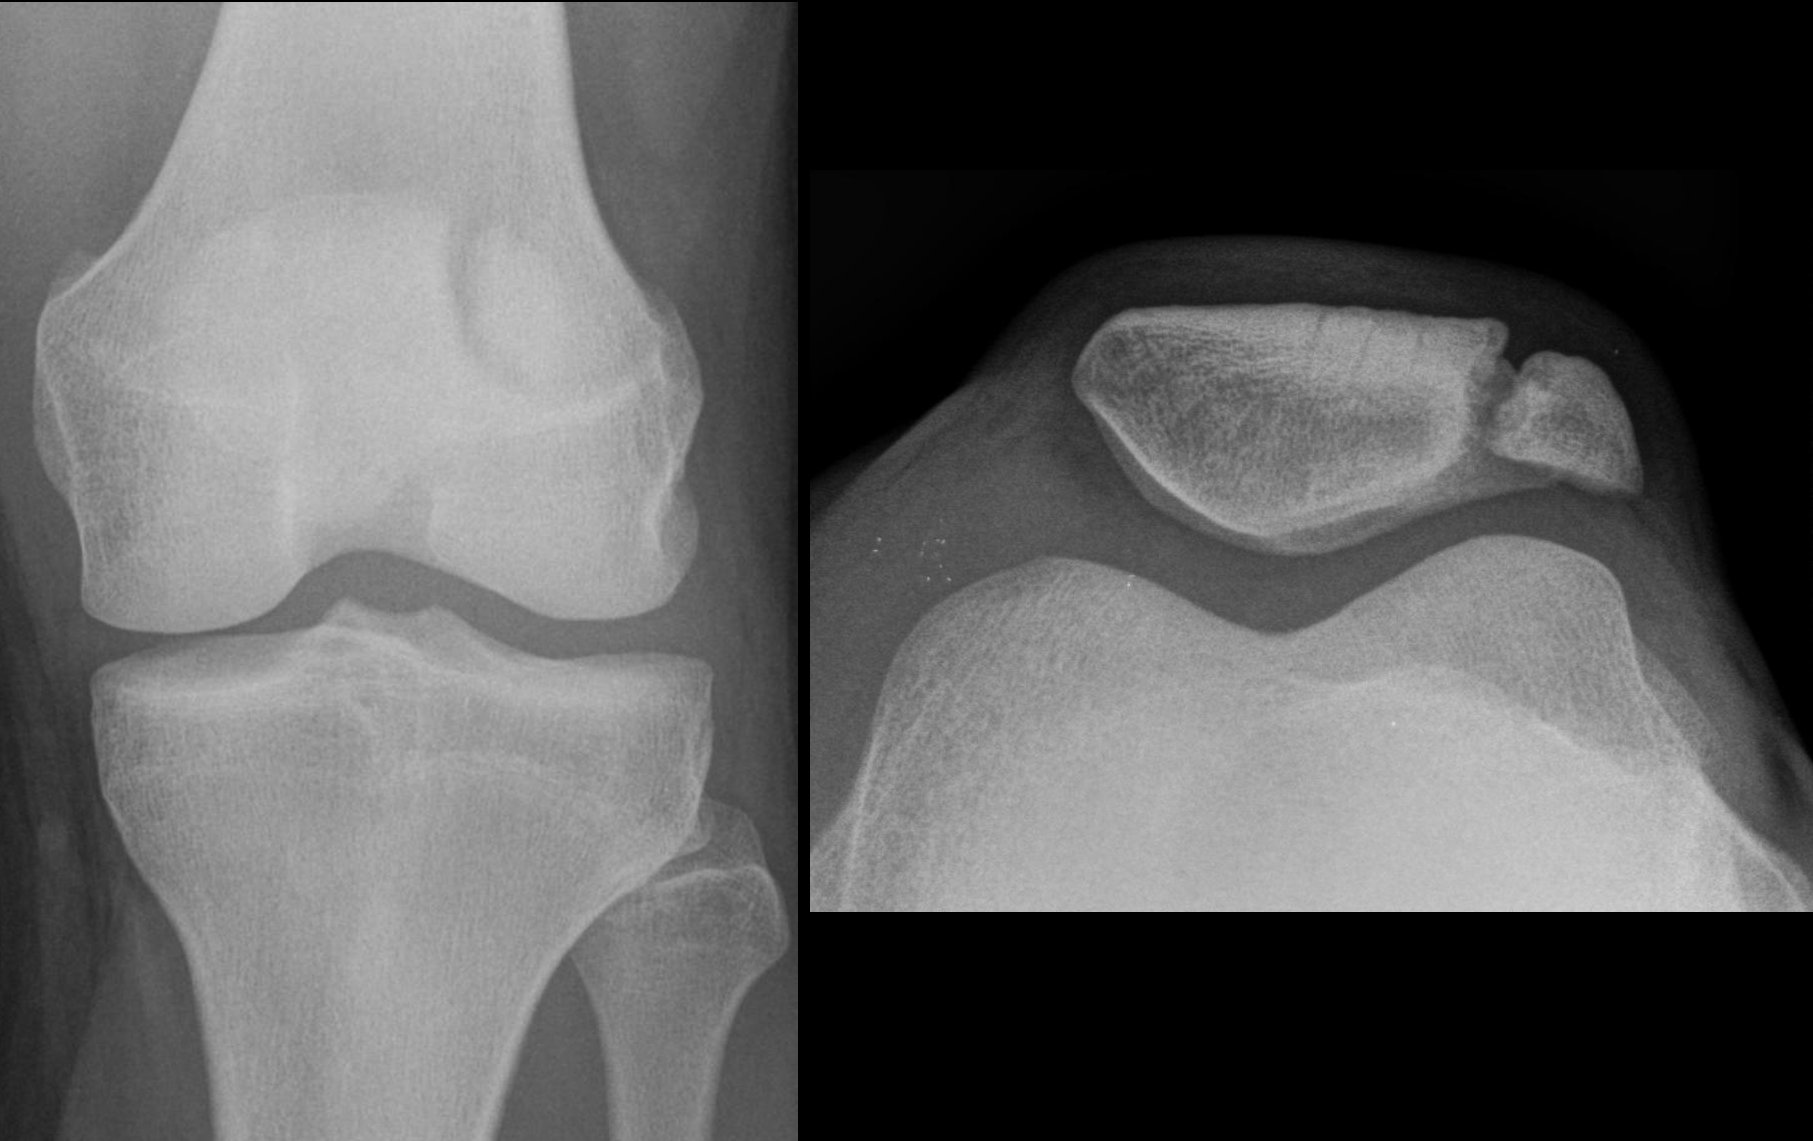

A patella, or kneecap, seen from the front and side of the leg Wikipedia